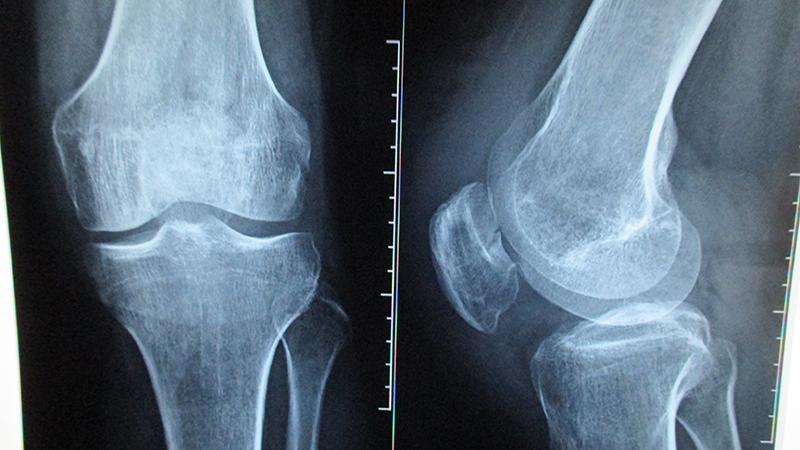

- Вторая стадия. Болезненные ощущения усиливаются. Появляются признаки воспалительного процесса. На 2 стадии рентген позволит увидеть пораженную область и ее отделение от здоровой ткани. Часто пациенту ставят неправильный диагноз – синовит.

- На последней стадии происходит полное отслаивание некротизированной области. У человека присутствуют сильные боли, усиливаются симптомы воспалительного процесса. Рентгеновские снимки четко показывают дефект в области коленного сустава, пораженный хрящевой обломок.

Это наиболее информативные методы диагностики, позволяющие определить область поражения и стадию заболевания. Выявить развитие воспалительного процесса позволит биохимический и клинический анализы крови.